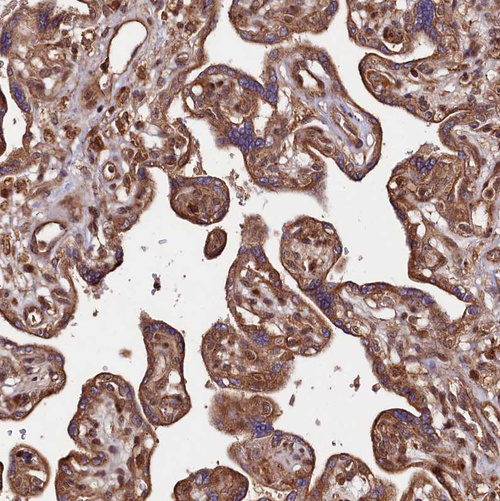

Immunohistochemical staining of human testis shows moderate cytoplasmic positivity in cells in seminiferous ducts.